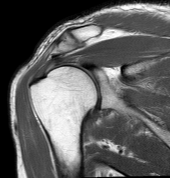

Coronal:

![]() |